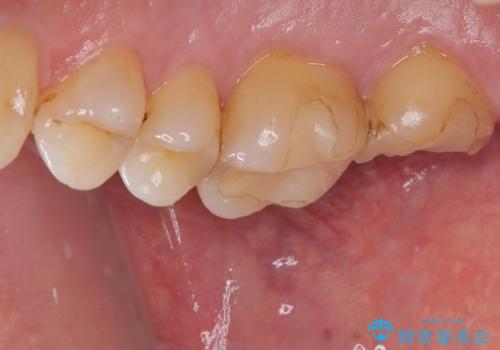

- 食事の時に奥歯が欠けて冷たいものがしみることを主訴として来院された患者様です。

虫歯が詰め物の下で広がっていたこと、もともとの詰め物が大きく健全な歯の量が少なく噛む面に強い力がかかったことが原因で歯が欠けてしまった事が考えられます。

精査の結果、歯肉縁下に破折は認めれられませんでした。

部分的な詰め物では再び割れてしまう可能性が高いため、虫歯を除去し、オールセラミッククラウンにて補綴することとしました。